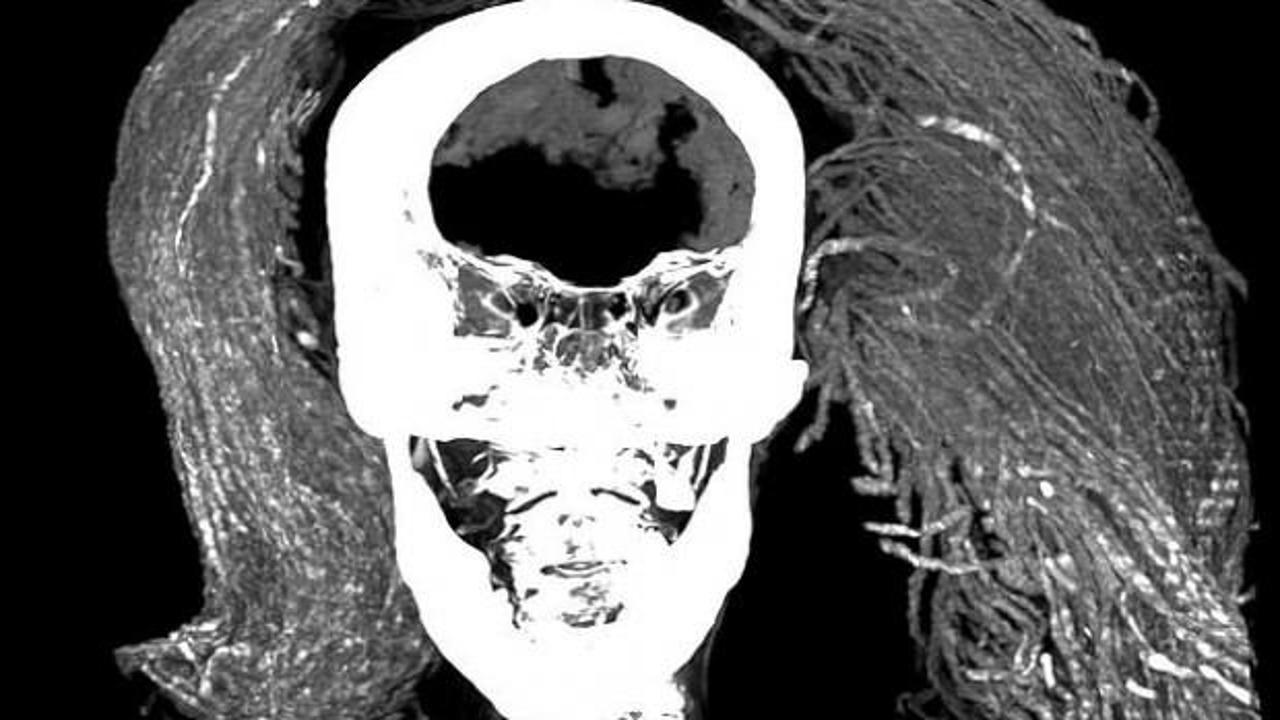

Frontiers in Medicine adlı hakemli dergide bugün (2 Ağustos) yayımlanan araştırmayı yürüten ekip, bilgisayarlı tomografi taraması ve X ışını kristalografisi gibi gelişmiş yöntemlerle kadının derisini, saçını ve peruğunu inceledi.

Mısır'da yaklaşık 90 yıl önce bulunan "çığlık atan mumyanın" gizemi çözülmüş olabilir. 3 bin 500 yıl kadar önce öldüğü düşünülen kadın hakkında yeni bilgiler edinen bilim insanları, mumyanın çarpıcı yüz ifadesi için de bir açıklama sundu.

Yaklaşık 3 bin 500 yıl önce öldüğü düşünülen bu kadının ağzı çığlık atar gibi, ürkütücü bir şekilde açıktı. Bilim insanları o zamandan beri bu alışmadık yüz ifadesine açıklık getirmeye çalışıyor.

Bu kanıtların özensiz bir mumyalama yapıldığı teorisiyle çeliştiğini söyleyen ekip, kadının ifadesinin nadir görülen, ani bir ölüm sertliği biçiminden kaynaklanabileceğini öne sürüyor.

Bilim insanları kadının ölümünden sonraki 18 ila 36 saat içinde, vücudu gevşemeden veya çürümeden önce mumyalanmış ve bu yüzden ağzının açık kalmış olabileceğini düşünüyor.